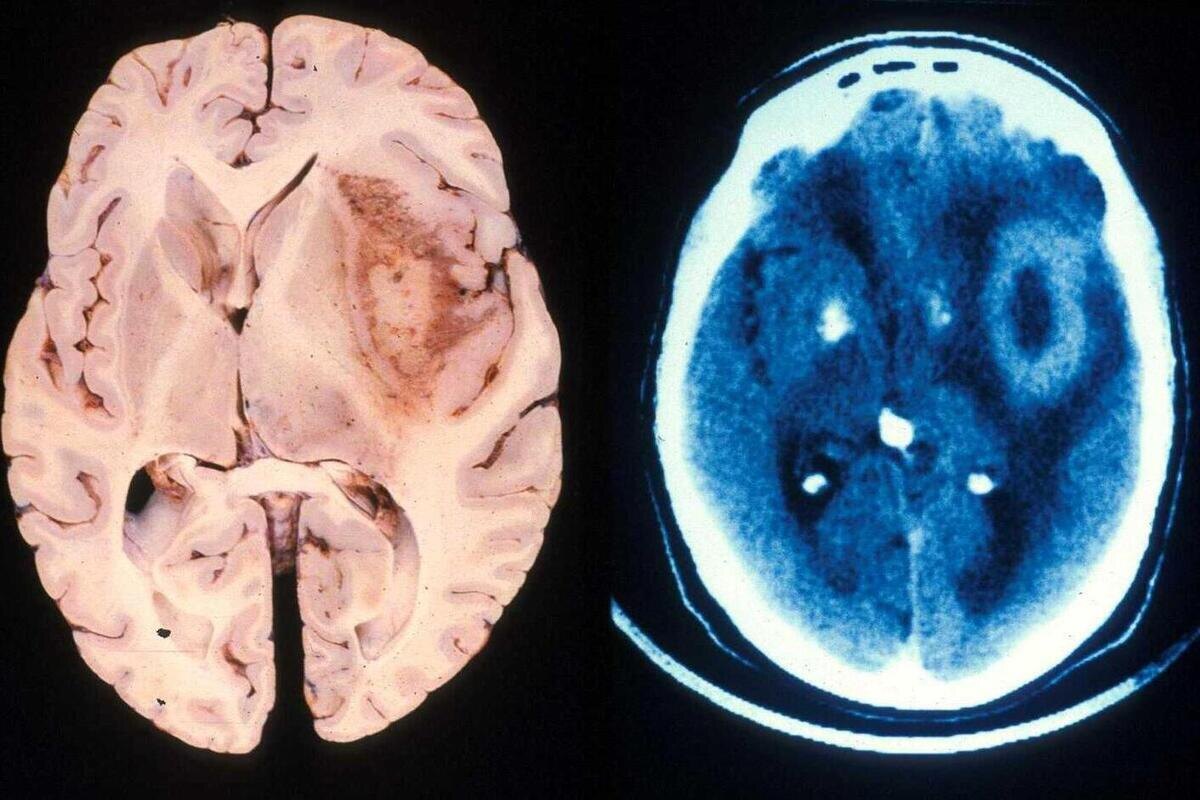

Шаг 2. Пройдите необходимую диагностику.

Основной метод выявления опухоли —

магнитно-резонансная томография (МРТ) головного мозга с контрастированием. Это безболезненная, безопасная процедура, которая даёт чёткую картину происходящего внутри черепа.

Компьютерная томография (КТ) тоже может использоваться, но МРТ информативнее для мягких тканей мозга.